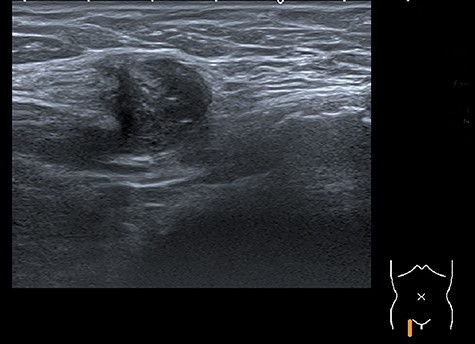

A 44-year-old multiparous woman (gravida 2, para 2), with a gynaecologic medical history of two caesarean sections at the age of 26 and 31, presented with a painful non-reducible mass in the right inguinal region without fever or other alarming symptoms. Two months prior to presentation a total laparoscopic hysterectomy was performed (without a salpingo-oophorectomy) because of menometrorrhagia. The intact uterus was removed vaginally and there were no complications in the postoperative phase. Histopathological analysis of the uterus was consistent with the preoperative diagnosis of adenomyosis. Additionally, two leiomyomas were found, one subserosal and one intramural, with a maximum diameter of 0.8 cm. Clinical examination revealed a palpable non-reducible regular mass of 3.0 ×2.0 cm in the right inguinal region near the round ligament of the uterus. Inguinal ultrasonography (US) showed a 2.2×1.4 cm hypoechoic solid mass suspicious for malignancy (Fig. 1). Because of the initial suspicion for malignancy, diagnostic workup also included an ultrasound of the abdomen and a chest X-ray, which showed no abnormalities. Laboratory investigations including white blood cell count, kidney and liver function were within normal ranges. Serology for Bartonella henselae antibodies was negative excluding cat-scratch disease. An ultrasound-guided biopsy was performed to obtain histology. Microscopic examination of the biopsy showed a leiomyomatous lesion, without signs of malignancy. The surgeon performed a resection of the mass. During the procedure, the mass was located proximal of the inguinal ligament and fixated in the inguinal ring. The mass was removed without any complications. Inspection of the specimen revealed a 1.8 × 1.8 × 1.5 cm white–gray regular mass surrounded by yellow–gray tissue. The histologic findings were consistent with extrauterine adenomyoma (Fig. 2). The patient was discharged within 24 h after surgery. The patient remained asymptomatic without any signs of recurrent disease after 1.5 years of follow-up.

Image of the inguinal ultrasound that shows an inhomogeneous round mass surrounded by subcutaneous fat tissue.